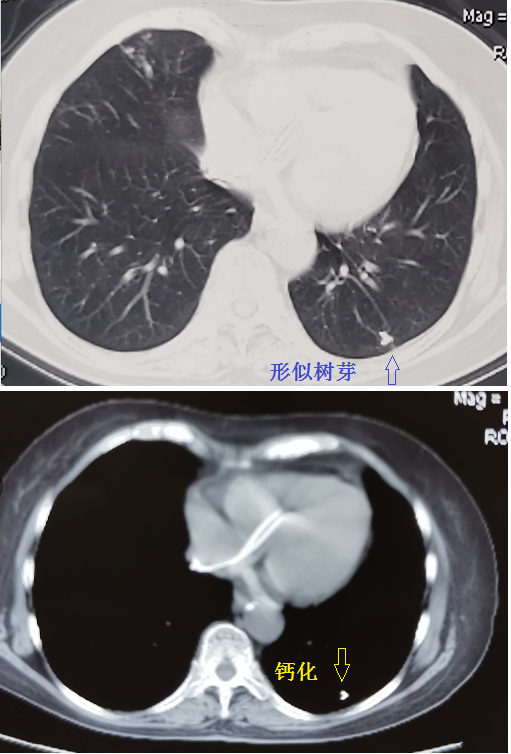

树芽征,即CT上形似树芽的征象,是由于小气道扩张,里面充满脓液、黏液、肉芽肿或炎性细胞,从而形成的。

从肺窗看到树芽征,要看纵隔窗,有时候是无意义的钙化,见图2。